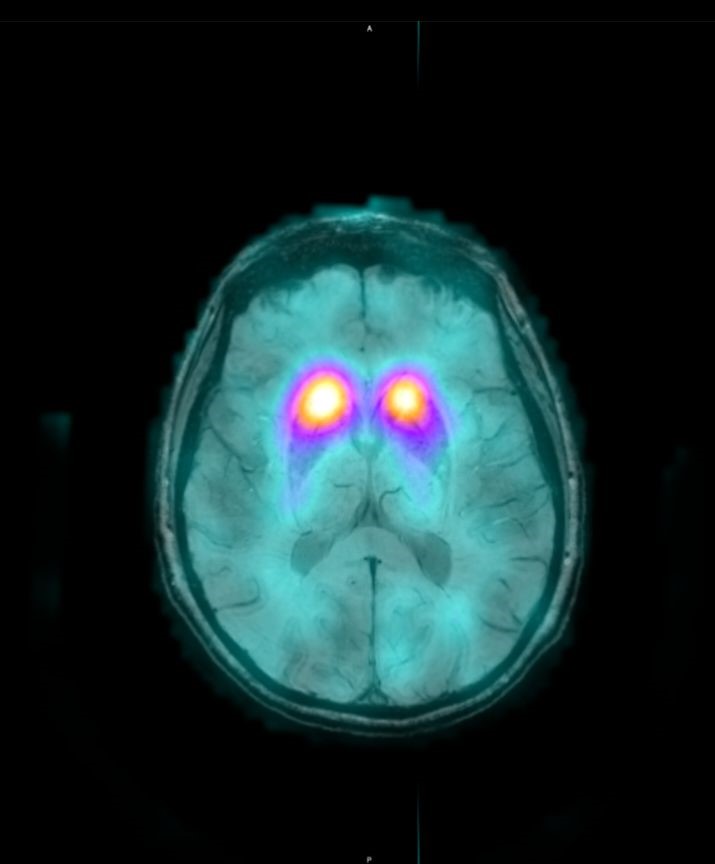

Το Lu-177 PSMA αποτελεί μια στοχευμένη ραδιονουκλιδική θεραπεία για ασθενείς με ορμονοάντοχο μεταστατικό καρκίνο του προστάτη (mCRPC), αξιοποιώντας τη υπερέκφραση του PSMA (Prostate-Specific Membrane Antigen) στα καρκινικά κύτταρα. Προηγείται PSMA PET/CT για ακριβή χαρτογράφηση της νόσου και επιβεβαίωση επαρκούς πρόσληψης του ραδιοφάρμακου. Το Lu-177 PSMA συνδέεται στους PSMA-υποδοχείς, επιτρέποντας στοχευμένη ακτινική δράση υψηλής κυτταροτοξικότητας σε μεταστατικές εστίες οστών και μαλακών μορίων. Η χρήση εξειδικευμένων δοσιμετρικών εργαλείων επιτρέπει την ποσοτική αποτίμηση της δόσης σε κρίσιμα όργανα (π.χ. σιελογόνοι αδένες, νεφροί, μυελός) και στον όγκο, συμβάλλοντας σε εξατομικευμένη θεραπευτική προσέγγιση. Μετά από κάθε κύκλο πραγματοποιείται PSMA PET/CT ή FDG PET/CT (όπου ενδείκνυται), καθώς και στενός αιματολογικός έλεγχος για αξιολόγηση της ανταπόκρισης και των πιθανών τοξικοτήτων. Η θεραπεία έχει αποδειχθεί ιδιαίτερα αποτελεσματική στη μείωση του καρκινικού φορτίου, στη βελτίωση του πόνου, στη μείωση των επιπέδων PSA και στη σημαντική παράταση του προσδόκιμου επιβίωσης σε ασθενείς με εκτεταμένη και ανθεκτική νόσο.